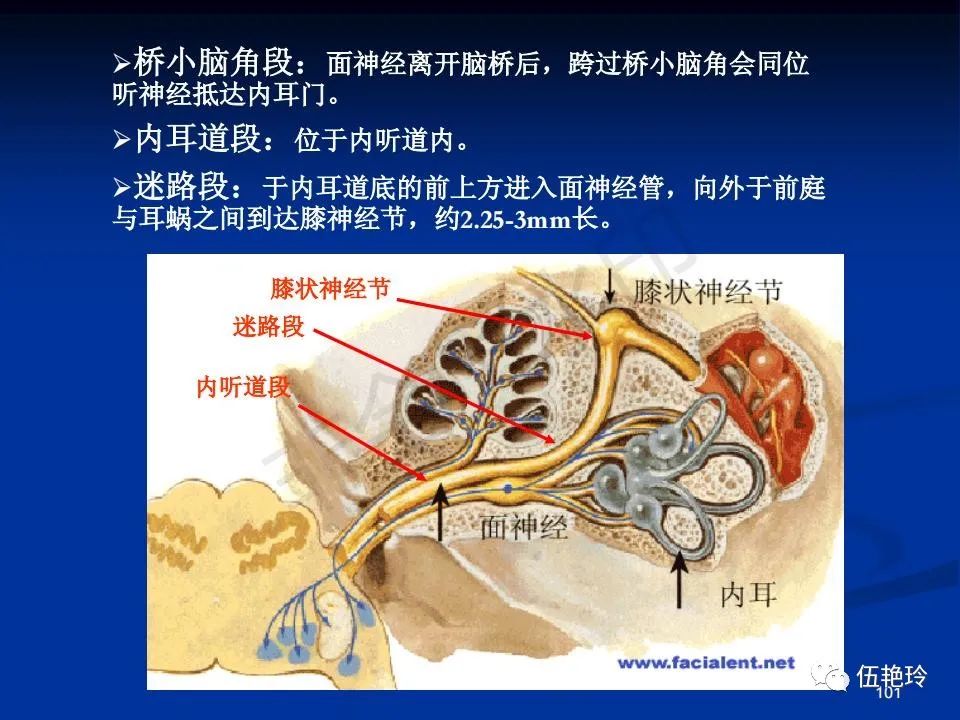

耳与面神经的解剖